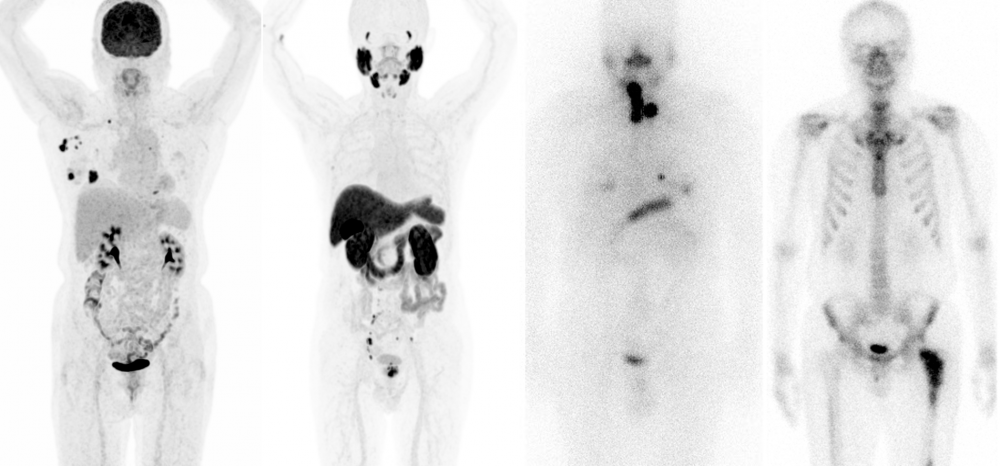

진료면에서 감마카메라, 단일광자단층촬영 (SPECT/CT), 양전자방출단층촬영

(PET/CT)을 통한 감마영상과 PET영상 건수는 지속적으로 상승하여 50 여종 가량의

다양한 영상 검사 및 핵의학 치료 들을 2024년 기준 한양대 서울병원 약 7천 건,

한양대구리병원 약 4천 건을 시행하고 있으며 명실상부한 한양대학교 의료원의 중심

진료과로 자리 잡고 있습니다.